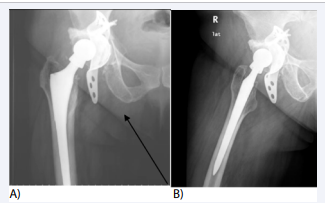

Pelvic heterotopic ossification may be present in young active patients and usually results to muscular injuries that lead to intramuscular hematoma formation. This hematoma may lead to ectopic bone mass formation which according to its size and location may irritate the sciatic nerve. We already have published an analogue case and our findings were similar to those reported by Lopez et al some years later [34,35]. The formation of heterotopic bony mass usually follows injuries near to the tendon bone insertion site. In both cases the ectopic bone was close to the sciatic tuberosity (Figure 3),

Figure 3: Anteroposterior (3A) pelvic and lateral (3B) right hip x-rays Two circumferential bony masses are pointed by white arrows. CT scan images (3C and 3D) where the ectopic bone is pointed by black arrows. MRI images (3E and 3F) where the pathology is pointed by white arrows.

where the muscles of the flexor compartment of the thigh mostly originate. In our case symptoms where increased while the patient was sitting. In both cases the size of the ectopic bony tissue was considerable, able to affect the ischiofemoral space, causing a ‘kind’ of deep gluteal syndrome (DGS), as described above. After the ectopic bone removal the patients recovered fully, without signs of recurrence in at least 2 years follow up period. In both cases the symptoms of the affected hip were mild and could have been under-estimated. Electromyography findings may be helpful as long as were indicative in our case (deep peroneal nerve dysfunction with pathological measurement of f-wave latency). Lopez et al, in order to differentiate diagnosis performed a selective L4-L5 foraminal nerve root block, which was negative [35]. So, in similar cases at least an antero-posterior pelvic x-ray should always be thoroughly reviewed.